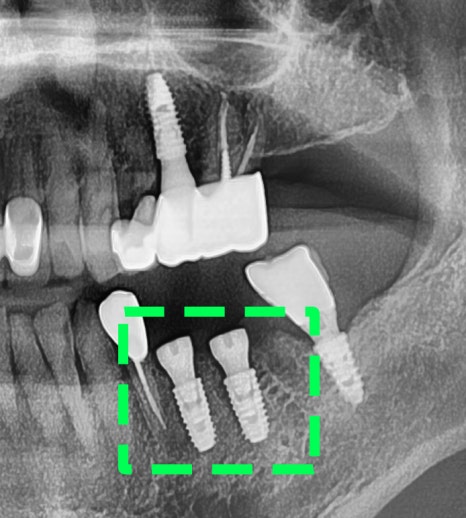

【 최종 세팅 및 수술 완료 】

맞춤형 어버트먼트와 크라운 제작까지

모두 완료되어 최종 세팅을 해드렸습니다.

윗니와 아랫니, 그리고 전체적 교합에

문제가 없는지 한 번 더 체크해줍니다.

또, 착용하고 나서

불편함이 느껴지는 부분은 없는지

여쭤보았으나,

크게 불편한 곳은 없으셔서

살짝 조정만 해드리며 끝났습니다.